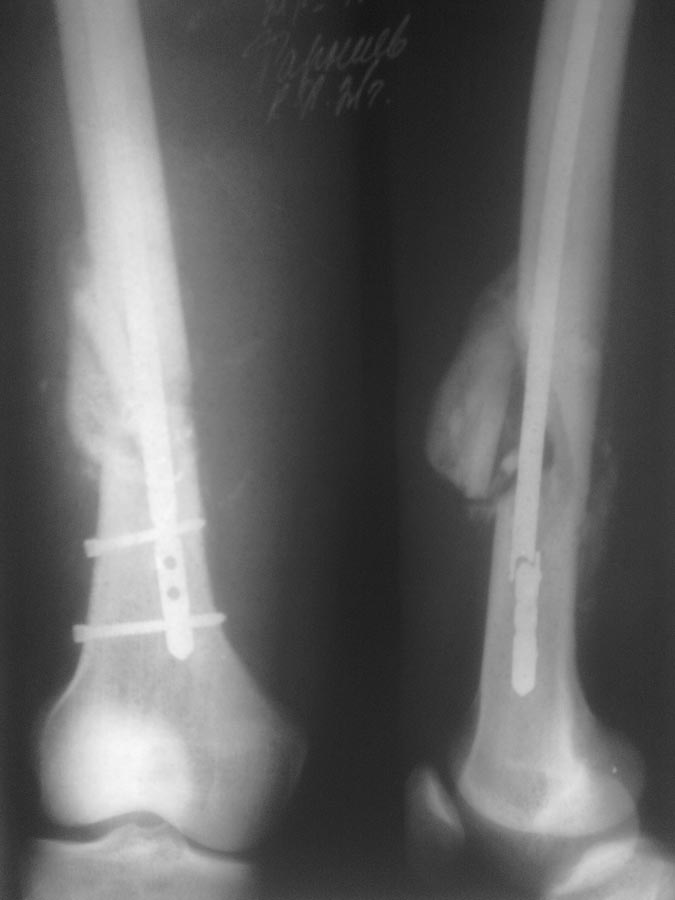

> Пациенту ровно полтора месяца назад проводилось оперативное лечение

> оскольчатого перелома н/3 бедренной кости БИОС.

> Гвоздь № 9. Антеградно. Место перелома не открывалось. Возраст пациента

> 21г. Со слов нагрузку давал не более 30 проц. от веса тела с четвертой

> недели. На 45 день гвоздь ломается, неосторожно перевернулся в кровати.

> Вопрос: что делать? Заранее спасибо!

1.  Не использовать на бедре гвозди диаметром 9 мм

2. Не использовать штифты этого и других сомнительных производителей на

людях.

3. Удалить проксимальные, дистальные винты и проксимальный отломок гвоздя.

4. Рассверлить канал до уровня перелома до 13-14 мм.

5. Дистальный отломок гвоздя не трогать.

6.Перелом не открывать.

7. Заштифтовать гвоздем (см. пункт 2) диаметром 12-13 мм.

8. Заблокировать статически по два винта сверху и снизу.

9. Разрешить раннюю полную нагрузку.